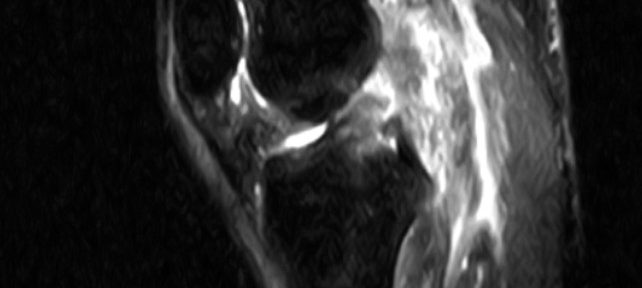

ACL Tear Natural Healing Case Report #50Case 50 | Natural Healing of Complete ACL Rupture: From Severe Ihara Type IV to Perfect Regeneration (ACLOAS Grade 0)